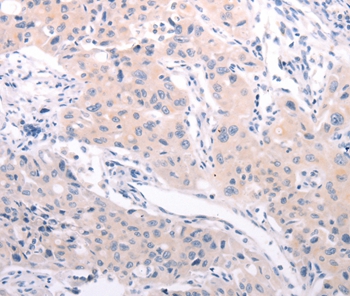

Immunohistochemical analysis of paraffin-embedded Human cervical cancer tissue using #36005 at dilution 1/30.

Immunohistochemical analysis of paraffin-embedded Human lung cancer tissue using #36005 at dilution 1/30.